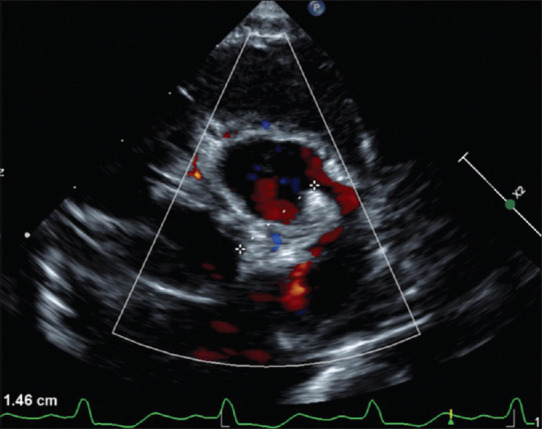

Anomalous left coronary artery from the pulmonary artery (ALCAPA) is a rare congenital heart disease, presenting either in isolation or with other cardiac anomalies. The most common presentation is congestive heart failure in infancy, though some may remain asymptomatic till adulthood. A 5-month-old infant with congestive heart failure was diagnosed to have ALCAPA with severe Left ventricular (LV) dysfunction. Unlike the more common variants where the left coronary artery (LCA) arose from the facing sinuses, the LCA arose from the left anterior nonfacing sinus of the pulmonary artery at a considerable distance from the left aortic sinus. This made direct reimplantation of LCA to the aorta challenging. LCA was reimplanted to the aorta using an extrapulmonary baffle made of an autologous pulmonary flap. The postoperative period was uneventful. The LV contractility improved during the follow-up. Early diagnosis and intervention with a novel surgical technique prevented irreversible cardiac complications and mortality.